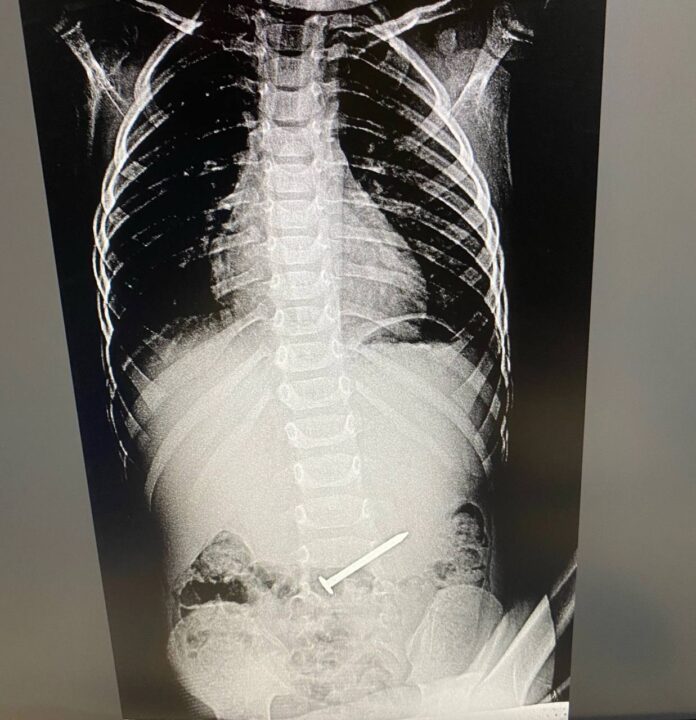

В альметьевскую Детскую городскую больницу попал трехлетний малыш. Выяснилось, что ребенок проглотил гвоздь. Произошло это во время игры. Позже мальчик все рассказал маме. Отмечается, что посторонний предмет в животе его совсем не беспокоил.

Маленького пациента экстренно госпитализировали. При проведении ФГДС выяснилось, что гвоздь длиной в пять-шесть см находился в двенадцатиперстной кишке. Ситуация осложнилась тем, что инородный предмет встал поперек. Гвоздь мог повредить стенки кишки.

Как сообщает пресс-служба Детской городской больницы, медикам удалось «стащить» инородное тело в желудок, что технически было тяжело. А уже после гвоздь извлекли корзинкой Дормиа.

Ребенок в течение четырех суток находился под наблюдением хирургов. Пациента уже выписали. Его здоровью ничего не угрожает.